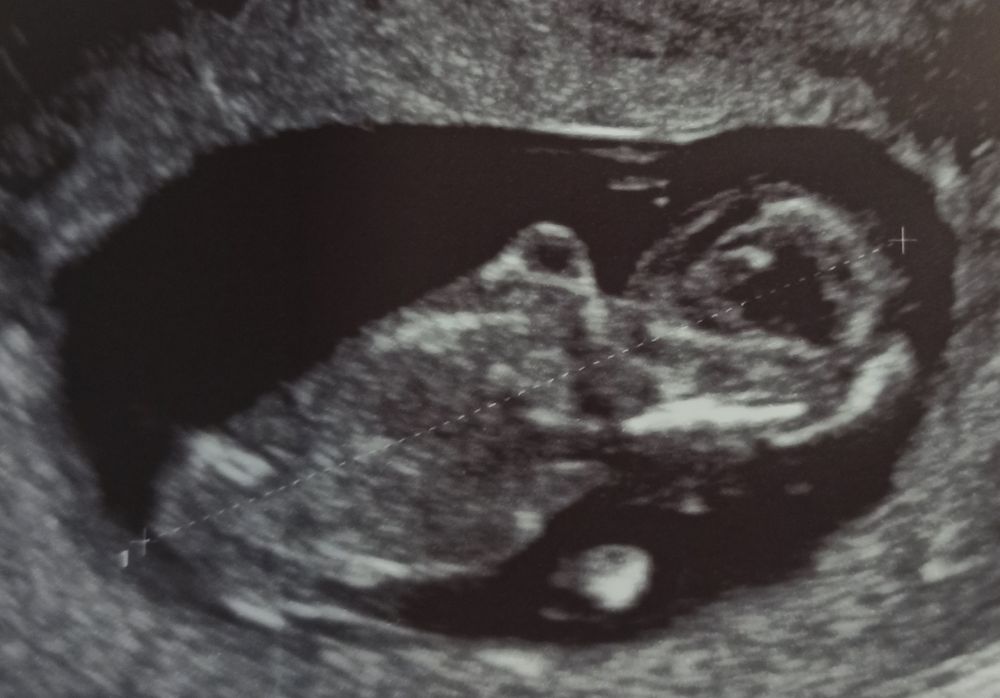

УЗИ 65 дпо (11+1) ❤🤞🤞🤞

Я стала переживать по поводу тахикардии плода, но я буду верить и надеяться, что ЧСС замедлится до нормы до 160 уд/мин, а как сейчас 170-180 уд/мин - это многовато на этом сроке (12 неделя), так частить сердечко может в норме до 9 недель, а далее должно замедляться постепенно. Домашним допплером пишет также до 170-178 уд/мин. Через неделю схожу снова на УЗИ, а потом, 2 мая будет 1 скрининг. Вот нашла табличку норм, не сильно, но превышает: